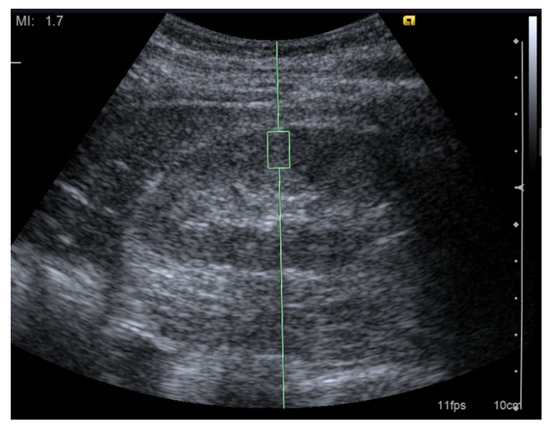

First, the target ROI must be carefully selected (Figure 1). Bob et al. investigated the potential factors influencing the results of the ARFI measurements. The depth of the ROI affects the SWV [23,24]. The push-pulse to induce shear waves tends to attenuate in deeply located tissues; thus, the elastography values correlate negatively with the depth of the ROI. Therefore, in contrast with the superficial organs such as the breast and thyroid, the depth of the ROI should be matched to the best extent. For this reason, it is preferable to perform SWE of the kidney with the patients placed in prone or unilateral positions. Most previous reports set the ROI at the renal cortex or parenchyma. It has been suggested that the measurement in the cortex is more reliable than in the medulla [25]. In patients with an impaired renal function, the kidneys show atrophic changes. The shortening of the kidney length and lessening of the parenchymal thickness in advanced kidney disease are widely recognized changes often observed by an abdominal ultrasound [26,27]. Although a careful determination of the ROI is required, the SWV can be measured reproducibly even in a patient with end-stage renal disease with a thin parenchymal thickness [28].

Figure 1.

Image of a shear wave elastography measurement. Representative ultrasound image for the measurement of renal elasticity using a Siemens Acuson S2000 ultrasound system (Siemens, Erlangen, Germany) with convex probes (4C1, frequency range: 1–4 MHz) and a mechanical index of 1.7. The region of interest was set perpendicular to the renal capsule.